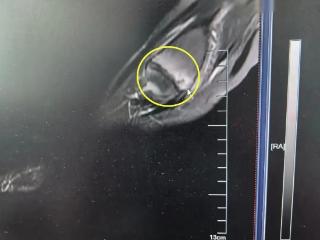

会分析、超能算,这个“医生助手”让诊疗过程智慧又高效